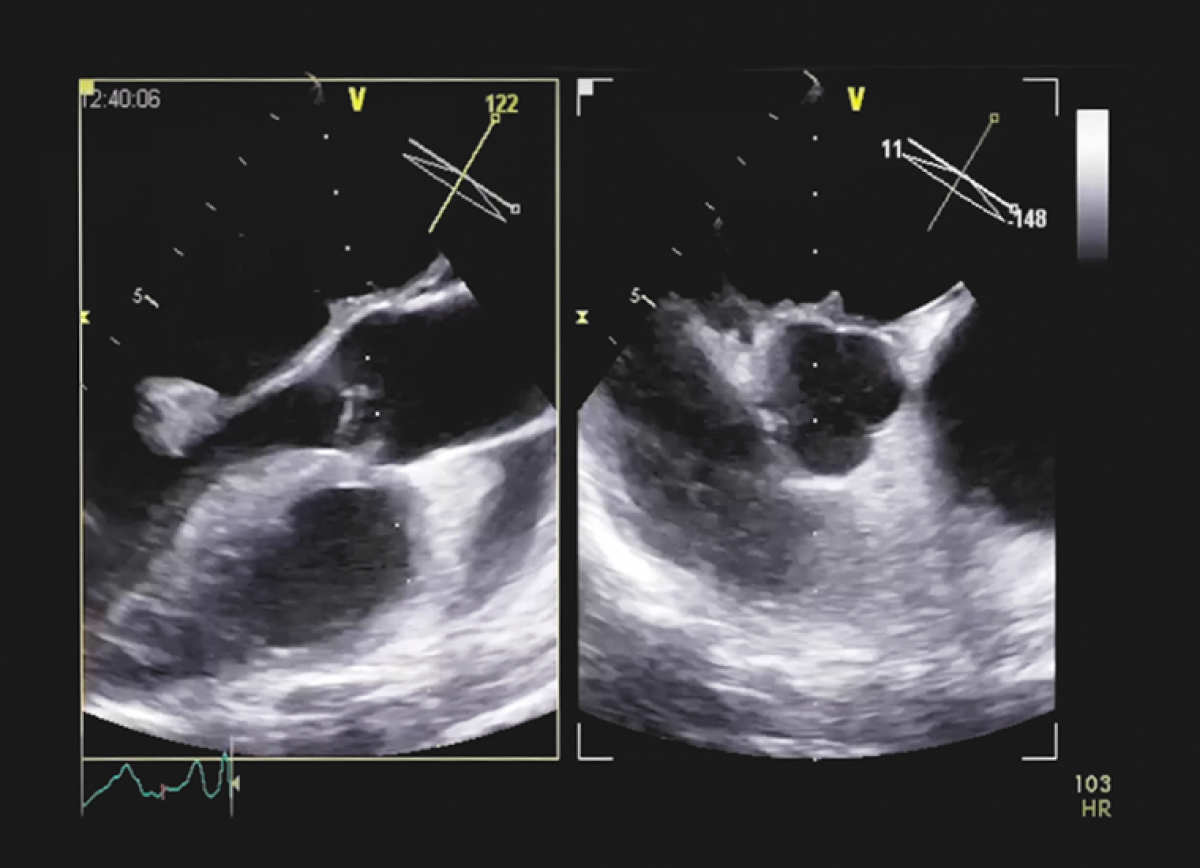

Pacjentka z pogorszeniem tolerancji wysiłku, długotrwałą gorączką i szmerem skurczowo-rozkurczowymi; w wywiadzie narkomania

Infekcyjne zapalenie wsierdzia z ciężką niedomykalnością mitralną i nadciśnieniem płucnym

Echokardiografia przezklatkowa i przezprzełykowa

Diagnostyka echokardiograficzna infekcyjnego zapalenia wsierdzia

Ocena niedomykalności mitralnej

Ocena ciśnień w krążeniu płucnym